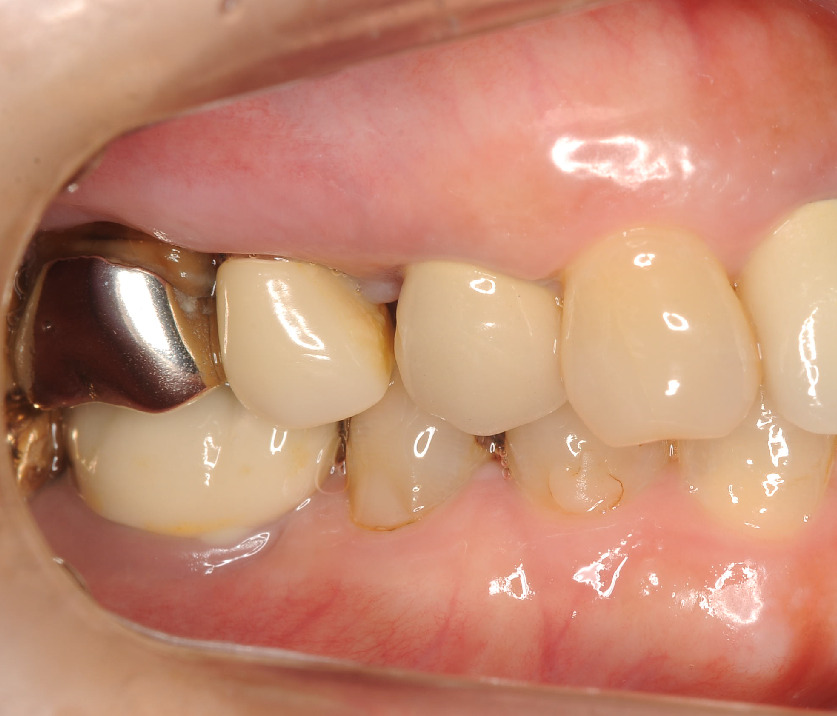

この方は50代女性で右側で咬めない事がお困りで来院されました。

確かにグラグラ。。。

レントゲンを見ると、

右上の4.5.6番の骨が3分の2位無くなっている状態で重症の歯周病でした。

歯周ポケットも7mm程ありました。